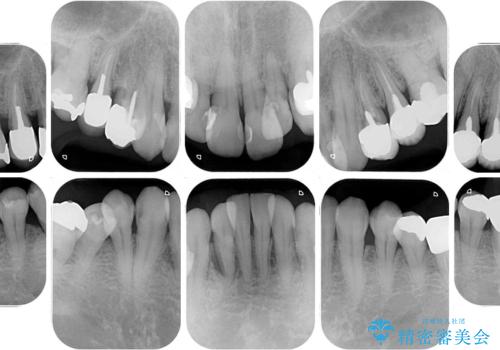

全体的に中等度の歯周病と診断されたため、歯周外科処置やインプラントによる咬合回復から進めて行き、矯正治療による歯列改善を行った後にオールセラミッククラウンにて補綴することとしました。

歯槽骨の再生治療を行ったため、外科処置後の静置期間がながくなり、4年弱の治療期間となりました。